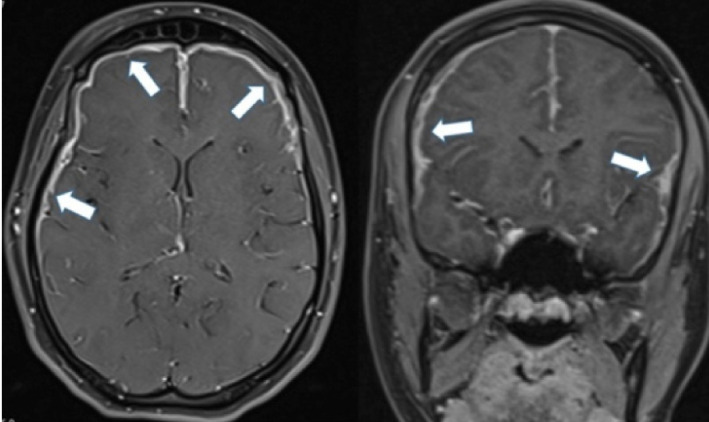

Pachymeningitis in a pediatric case of IgG4-related disease successfully treated with mycophenolate mofetil.

Abstract Image